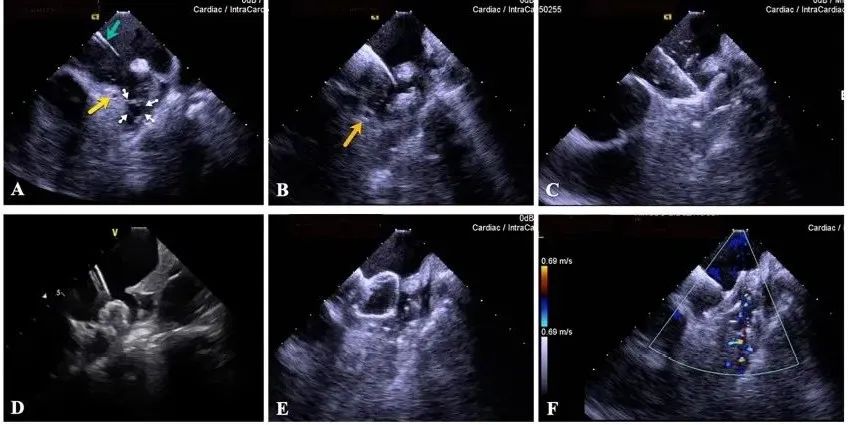

一種與心導(dǎo)管檢查相結(jié)合的超聲心動(dòng)圖診斷新興技術(shù),通過將超聲探頭置于心腔內(nèi)部,發(fā)射并接收超聲信號(hào),來(lái)精確獲取心臟解剖結(jié)構(gòu)、心臟血流動(dòng)力學(xué)等信息的實(shí)時(shí)成像。與其他影像技術(shù)相比,ICE技術(shù)具有操作簡(jiǎn)單、無(wú)輻射、安全性高、手術(shù)效率高、實(shí)用等優(yōu)勢(shì),ICE在很大程度上有望取代經(jīng)食道超聲心動(dòng)圖(TEE),成為電生理和結(jié)構(gòu)性心臟病領(lǐng)域的理想成像方式。

目前ICE技術(shù)已被應(yīng)用于左心耳封堵、房顫射頻消融、二尖瓣成形、房間隔缺損封堵等多種心臟介入手術(shù),應(yīng)用場(chǎng)景主要圍繞臟電生理、結(jié)構(gòu)性心臟病等領(lǐng)域,目前以電生理應(yīng)用為主。數(shù)據(jù)顯示,我國(guó)結(jié)構(gòu)性心臟病介入器械市場(chǎng)規(guī)模已從2017年的4億元增長(zhǎng)至2021年的20億元,年復(fù)合增長(zhǎng)率達(dá)48.3%;預(yù)計(jì)到2025年,該市場(chǎng)規(guī)模將達(dá)到104億元,可以預(yù)見ICE市場(chǎng)規(guī)模也將同步高速增長(zhǎng),未來(lái)市場(chǎng)發(fā)展空間廣闊。